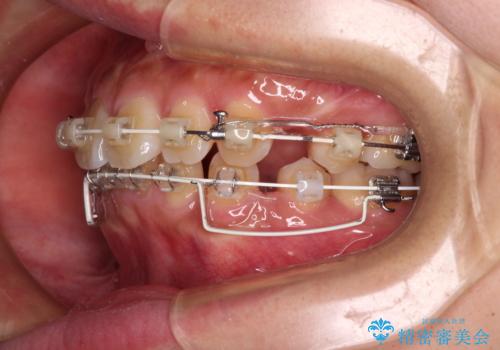

- 矯正装置

- 審美装置

- 前歯の突出感を気にして来院された患者様です。

咬合力が非常に強く、咬合力で前歯が前方に押し広げられており、上下唇に閉じにくさが認められました。

上下左右の第一小臼歯4本を抜歯し、ワイヤー装置にて矯正治療を行うこととしました。

強い咬合力により前歯の隙間がなかなか閉じられず、治療期間は長いものとなりましたが、横顔の印象が大きく変わるほど口元の印象を改善することができました。